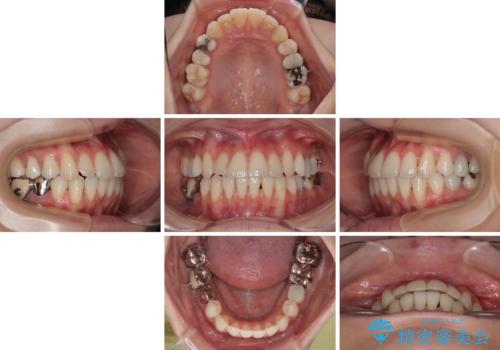

- 上下前歯のデコボコとクロスバイトを気にして来院された患者様です。

治療済みの処置歯が多いため、インビザラインを用いて矯正治療を行うこととしました。

下顎臼歯部にブリッジが装着されており、移動不可のため、IPR(歯と歯の間を削る)と歯列全体を拡大させることで、歯並びを整えていくこととしました。

インビザライン特有の奥歯の噛みにくさが治療後半に発現しましたが、無事に終了させることができました。